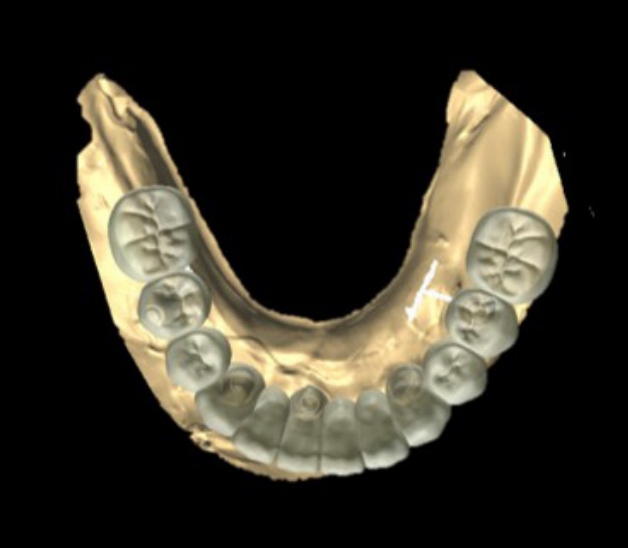

Fig. 7.

Ideal Implant positioning is planned with CAD software

jkda-2025-63-7-001f7.jpg

환자가 적응한 임시 의치를 모델 스캔(Medit T710, Medit, Seoul, Korea)하여 프린팅용 레진(Graphy Tera Harz SG-100, Graphy, Seoul, Korea)을 이용하여 3D 프린팅하였고, 출력된 의치에 방사선 불투과성 레진(G-æenial Universal Flo, GC, Luzern, Swiss)을 부착하여 레진 마커를 형성하였다. 레진 마커를 부착한 프린팅 의치를 장착한 채로 콘빔 전산화 단층촬영(CBCT, R2 Studio Q, Megagen, Seoul, Korea)를 촬영하였다(Fig. 6). 촬영한 CBCT 데이터와 의치 스캔 파일을 중첩하여 CAD 소프트웨어(R2 Studio Q, Megagen, Seoul)를 통해 이상적인 임플란트 식립을 계획하였다. 전후방 거리를 연장하여 적절한 캔틸레버를 부여하기 위해 전방부에 3개의 임플란트를 식립하고, 양측 후방부에는 약 30도 경사진 임플란트를 식립하도록 계획하였다(Fig. 7).